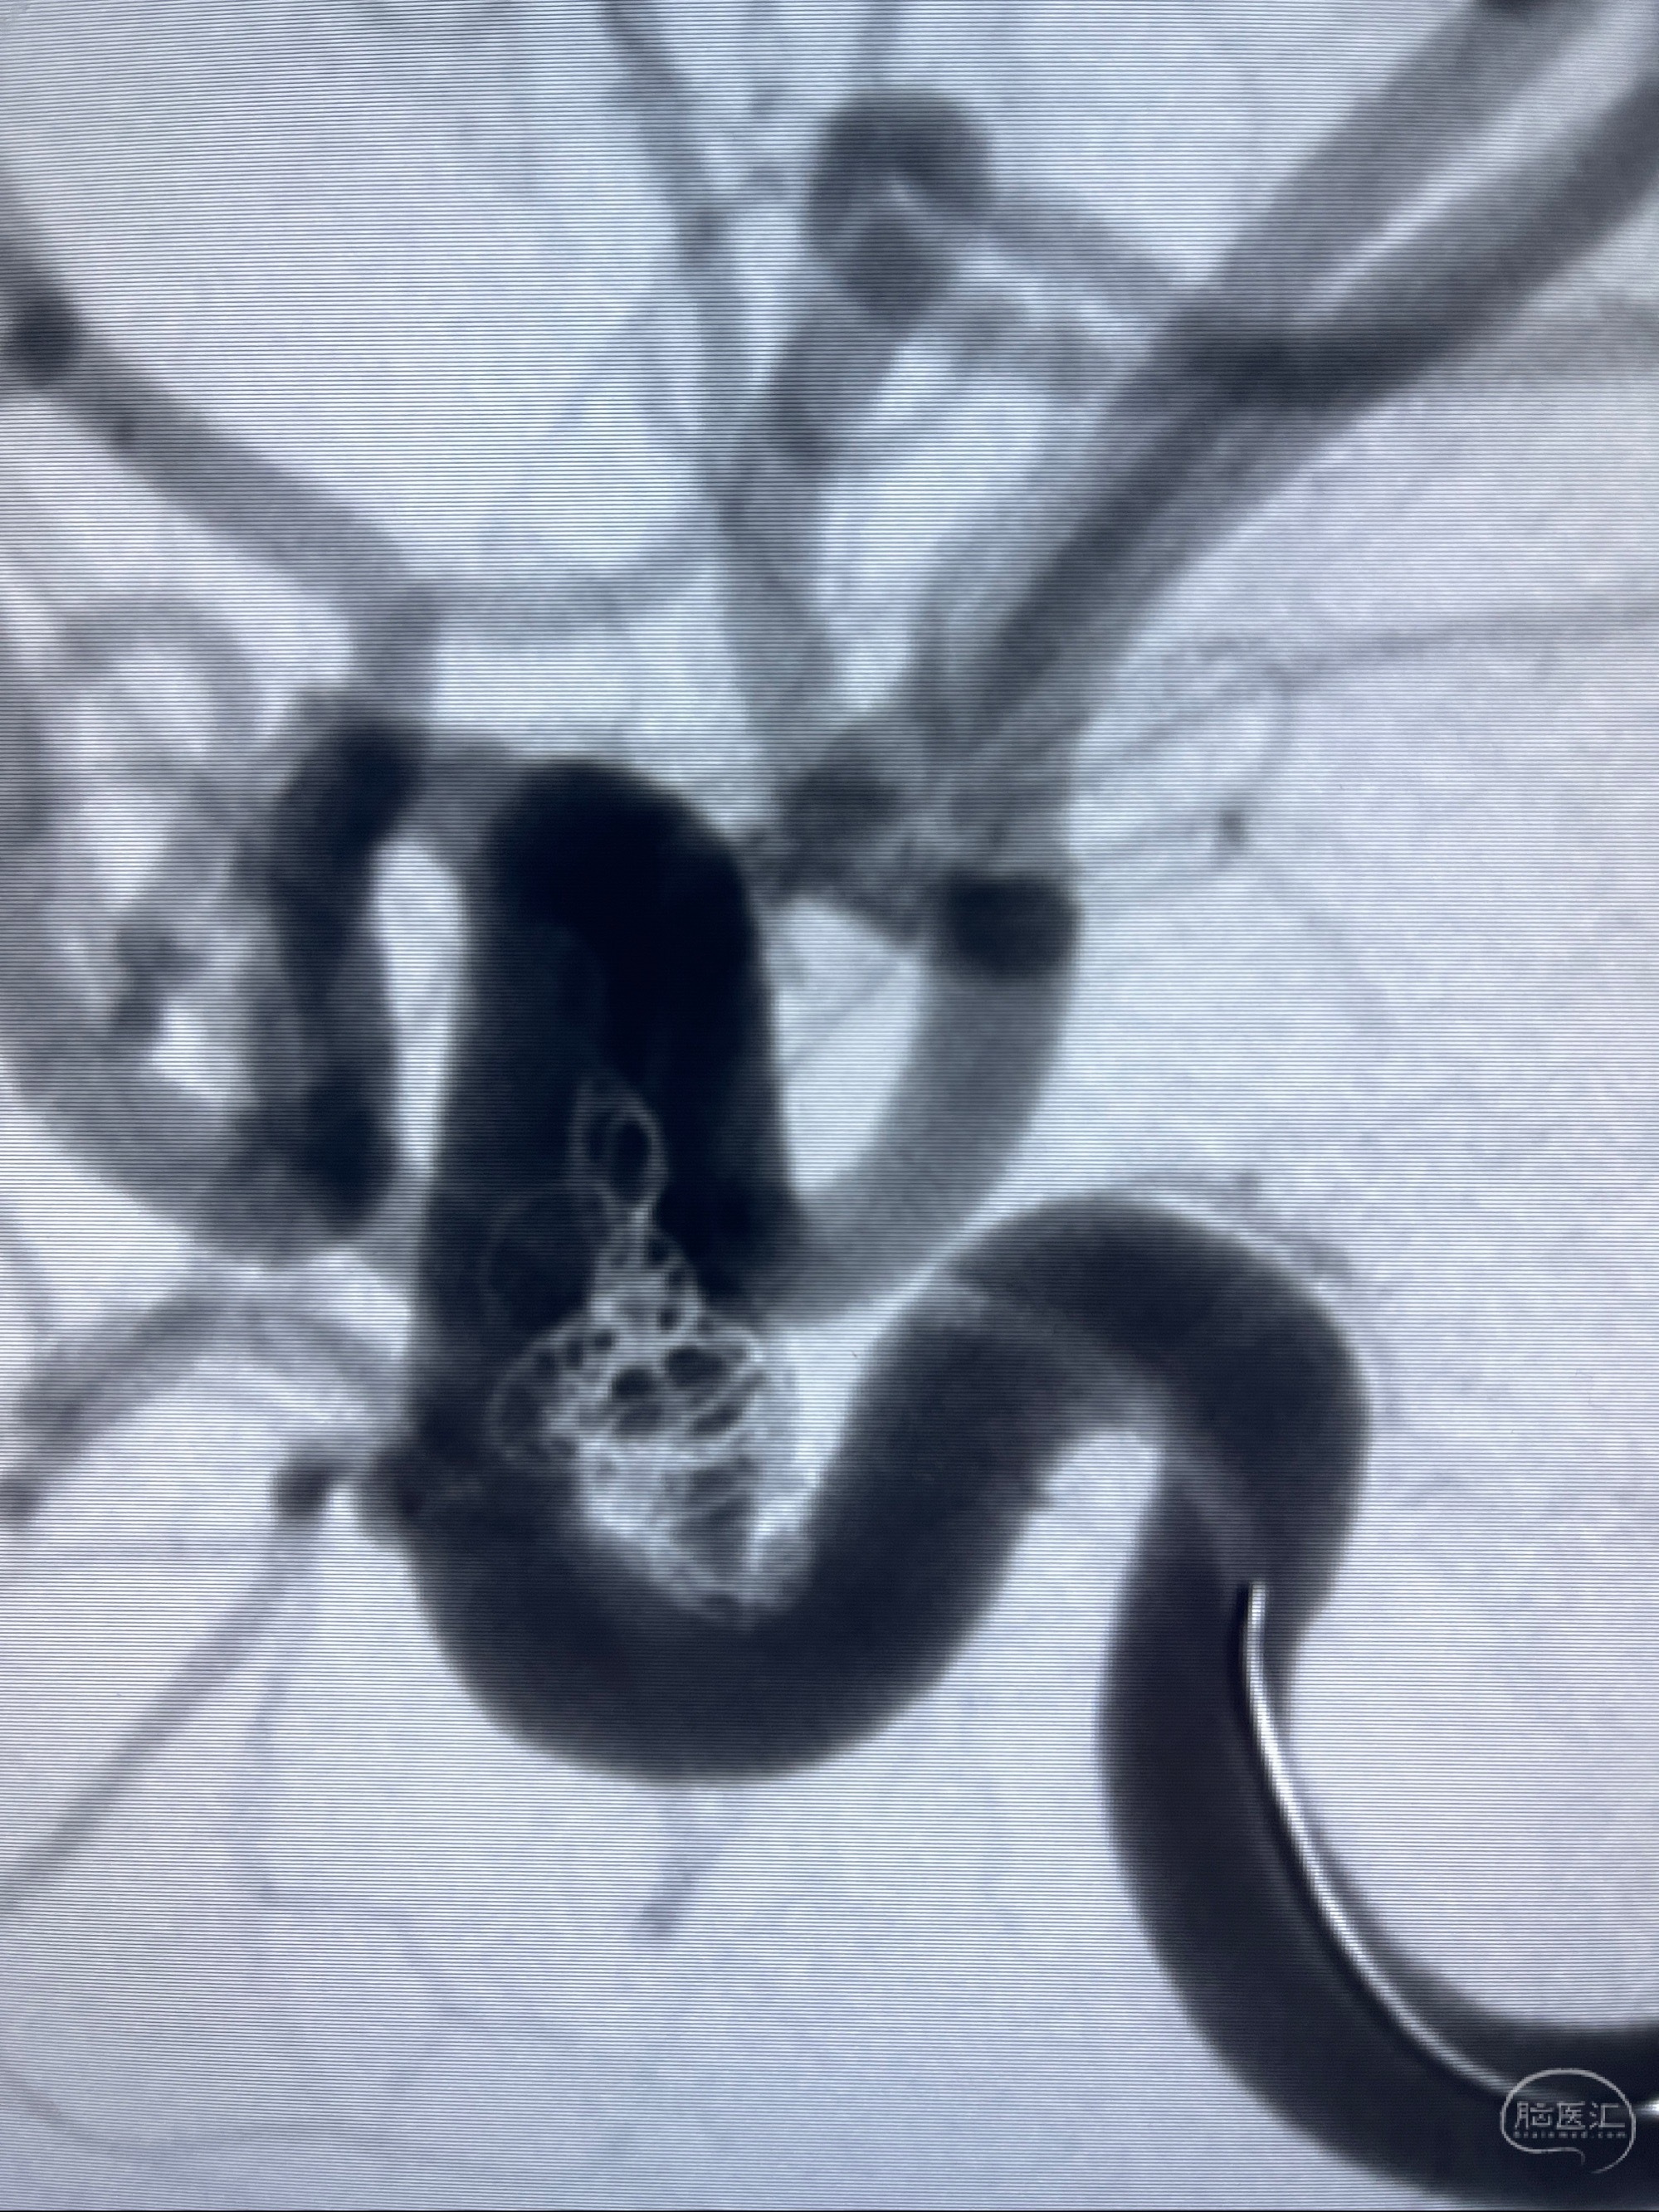

CTA示:右侧颈内动脉C6段见指向下方的突起,余左侧颈内动脉、双侧椎动脉、大脑前动脉、大脑中动脉、大脑后动脉及基底动脉走形正常,未见明显扩张及狭窄,局部未见明显瘤样扩张。

2023-07-27全脑血管造影:双侧颈内动脉眼动脉段动脉瘤,右侧较大

2023-08-01全麻下行双侧颈眼动脉瘤支架辅助栓塞

- pipeling4.5-20mm

- pipeline 4.0-20mm

术后即刻CT